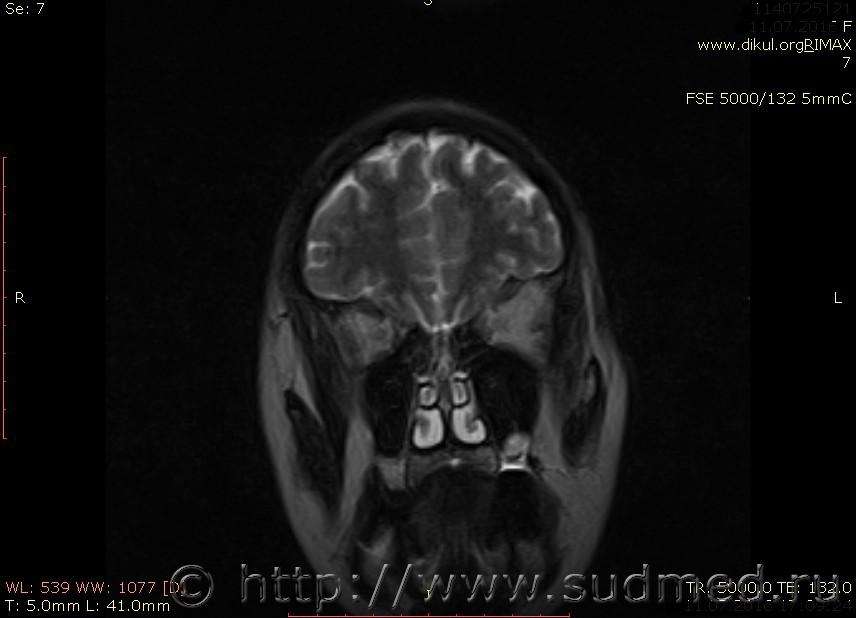

МРТ головного мозга показало: МР-данных за наличие очаговых изменений в веществе головного мозга на момент исследования не выявлено. МР-признаки нарушения соотношения в атланто-осевом суставе. Определяется ассиметрия положения зубовидного отростка С2 относительно боковых масс С1(справа 6,5; слева 4 мм.)

Сама по себе эта информация даёт основания подозревать вывих первого шейного позвонка, но однозначно не свидетельствует о наличии вывиха. Нужно смотреть на снимках наличие реакции со стороны мягких тканей, в т.ч. связочного аппарата, нужно анализировать особенности неврологической патологии, её динамику и проч.

Запрошен электронный вариант снимков из учреждения, где делалось МРТ. Т.к. с самого снимка делать копии не получается,очень мелкие кадры. Завтра попробую вставить в сообщение. (Но СМЭ снимок не смотрел, смотрел только мед.карту, в которой находилось описание МРТ).

Посмотрите пожалуйста снимки, надеюсь на них видны позвонки С1,С2?

Прошу прощения, попробую снова прикрепить файлы. Данные учреждения и пациента убраны.